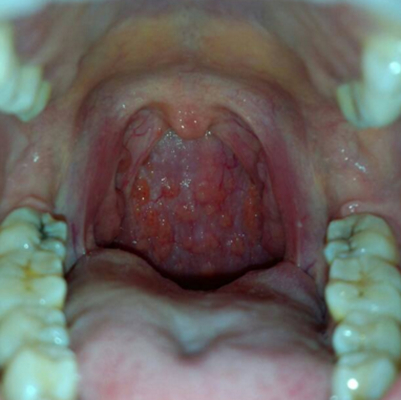

咽喉良性肿瘤